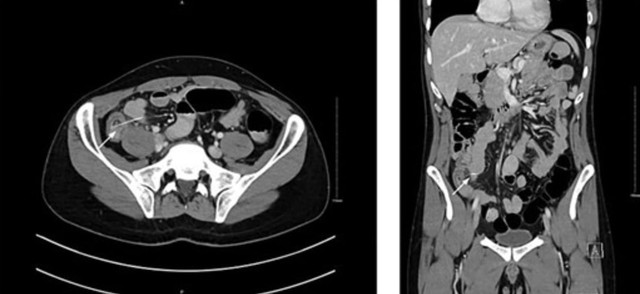

Các bác sĩ đã bối rối cho đến khi chụp CT phát hiện ra dị vật nhỏ có kích thước 3,7 cm, mà họ cho rằng đó là một chiếc xương vô tình nuốt phải từ bữa tối với thịt gà.

Họ đã yêu cầu phẫu thuật nội soi khẩn cấp để tìm hiểu thêm và phát hiện ra nguyên nhân: một chiếc tăm gỗ đã đâm thủng ruột, theo như Need To Know đưa tin .